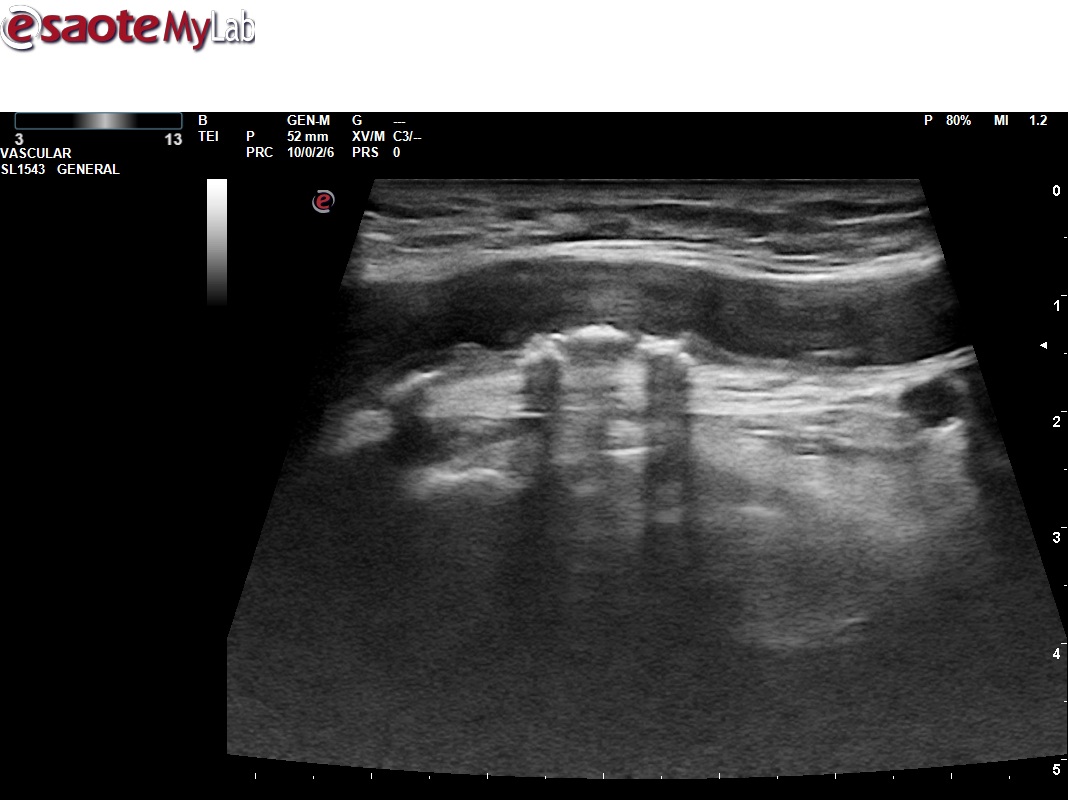

Mostramos el uso de la ecografía en el contexto de una actividad comunitaria, como es la celebración de puertas abiertas de un centro de salud por sus 25 años de apertura. Dentro de las múltiples actividades desarrolladas, se realiza una mesa de valoración de Riesgo cardiovascular (RCV) participando todos los estamentos, desde la unidad de atención al usuario (UAU) captando pacientes, como enfermería para valoración de factores de RCV, medicina para establecer SCORE, objetivos de control y puesto ecográfico para reestratificar a pacientes con bajo/moderado riesgo aplicando el protocolo VASUS de la SEMI (Sociedad Española de Medicina Interna).

La experiencia ha fortalecido el trabajo interdisciplinar, otorgando reconocimiento a todos los niveles asistenciales y visibilizando nuestra actividad clínica. Asimismo, ha estrechado el vínculo con los pacientes y dinamizado la incorporación de la ecografía en la práctica diaria. Además de manera destacada, en un elevado porcentaje de participantes se identificaron placas ateroscleróticas, modificando así sus objetivos de control y poniendo de manifiesto la gran utilidad de la técnica. Estos hallazgos subrayan la necesidad de abordar el infradiagnóstico de la aterosclerosis y refuerzan la conveniencia de integrar sistemáticamente la ecografía en la Atención Primaria.